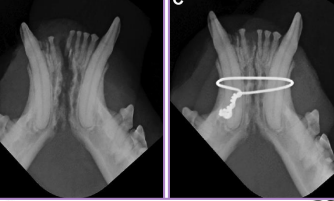

Symphyseal wiring: cats, cerclage wire between canines, 6-8w healed

Interdental splinting: acrylic/wire splinting, good for rostral, requires stable teeth